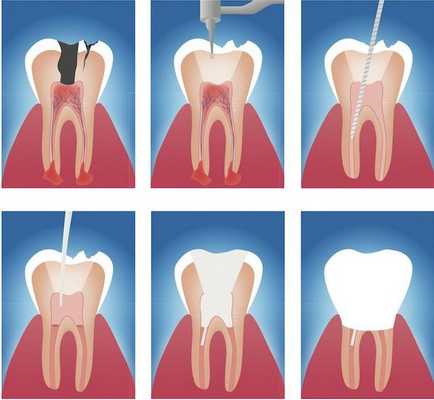

Этапы эндодонтического лечения:

- адекватное обезболивание;

- изоляция зуба или нескольких зубов, в которых будут проводится манипуляции, от полости рта;

- создание эндодонтического доступа (иссечение твёрдых тканей зуба или пломбировочного материала, закрывающих доступ в систему корневого канала;

- прохождение и определение длинны корневого канала (это длинна от устья до верхушки корня);

- создание корневого канала определённого диаметра и формы;

- введение в корневой канал лекарственных препаратов;

- пломбирование корневого канала;

- восстановление анатомии и функции зуба с помощью пломбировочного материала или ортопедической конструкции.

Последовательность действий в терапевтическом лечении:

- Обезболивание ;

- Изолирование пораженных участков (зубов), то есть наложение коффердама. Это важная часть лечения, так как обработка каналов будет происходить сильнодействующими веществами. Чтобы избежать ожогов мягких тканей.

- Удаление пломбировочного материала и других твердых тканей, препятствующих доступу к пораженным участкам;

- Очистка механичесим и медикаментозным способом каналов от микробов. Промывание и ирригация каналов растворами.

- Определение длины канала ;

- Формирование чистого корневого канала;

- Установка лекарства;

- Пломбирование корневого канала, во избежание попадания микробов на ранее пораженные участки;

- Восстановление функциональных и анатомических особенностей зуба пломбой или протезной конструкцией.